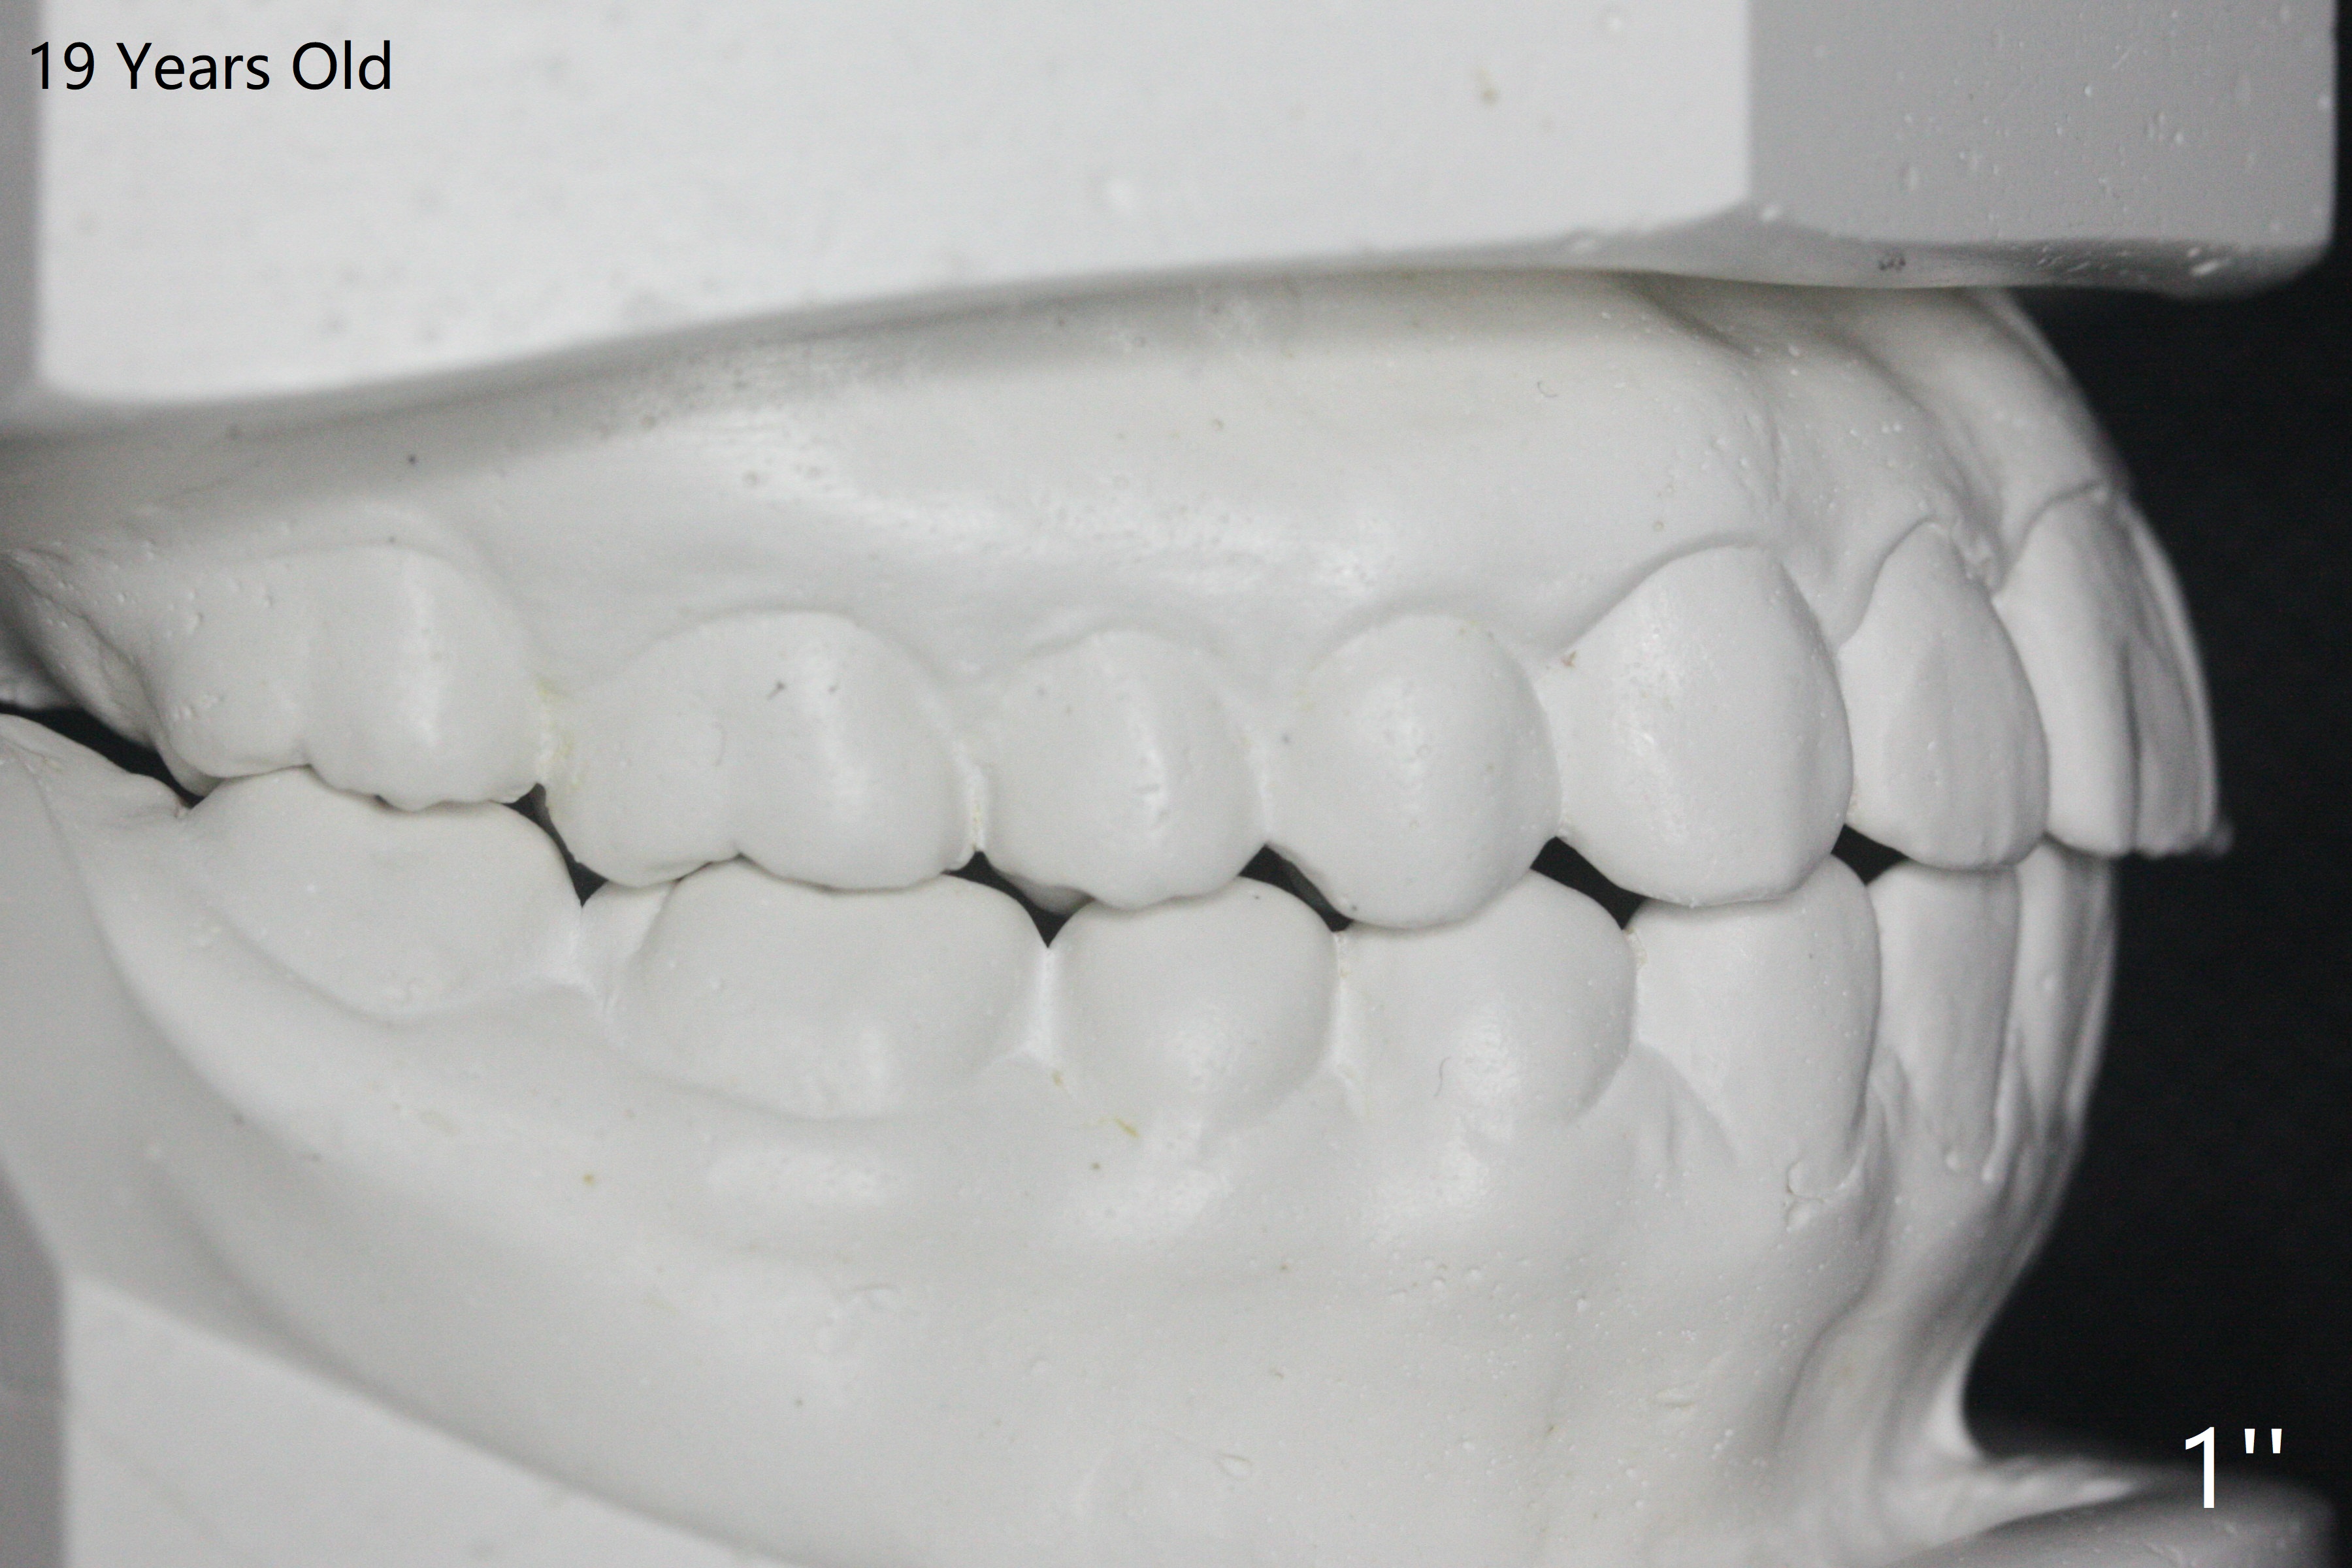

A 12-year-old woman has severe crowding including UL7 impaction (Fig.1-5), finishes non-extraction orthodontics at the age of 15 (Fig.1'-5') and returns for retainer remake at 19 (Fig.1''-5''). Four years post debanding, UL7 (Fig.4') seems to improve its position (Fig.4'').